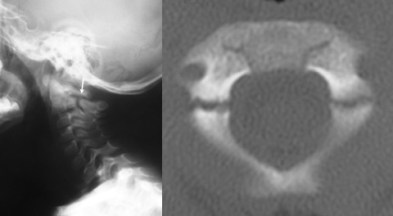

la fracture de l’odontoïde

elle entraîne une instabilité par rupture du pivot rotatoire atlo-axoïdien. il existe également une désaxation cranio-cervicale avec un bras de levier qui induit une cyphose évolutive.

elle est parfois peu visible chez l’enfant, il s’agit d’un décollement épiphysaire de l’odontoïde ou de la synchondrose neuro-centrale.

elle nécessite une réduction et arthrodèse par laçage postérieur C1-C2 avec greffe (type Gallié)

l’appartenance de l’os odontoideum aux lésions traumatiques ou malformatives est discutée, on a pu invoquer un traumatisme néonatal. cette pathologie peut être décompensée brutalement, elle est souvent découverte à la suite d’un trauma mineur.